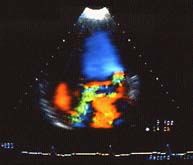

1. ECOCARDIOGRAFIA :emplea ondas sonoras para producir una imagen del corazon y ver como funciona. segun el tipo de estudio ecocardiografico que se realice puede determinarse el tamaño, la forma y el movimiento del musculo cardiaco.. al iguall puede mostrar como funcionan las valvulas cardiacas y como circula la sangre por el corazon.

1. ECOCARDIGRAMA TRANSESOFAGICO :es una prueba que muestra imagenes de su corazon usando ondas de ultrasonido. es un examen medianamente invasivo, en el que se introduce una sonda o tubo por la boca llegando hasta el esofago. el examen permite que el especialista vea de una forma mas cercana el funcionamiento del corazon ( cavidades, flujo sanguineo, valvulas etc.. )